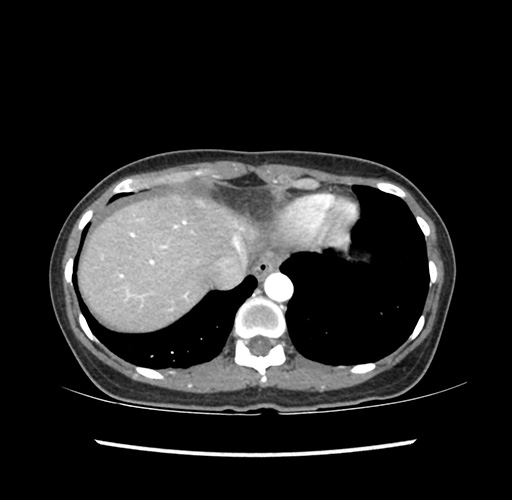

Imaging Analysis

Look through the patient's CT scan to identify any areas of concern for the necessary procedure.

Based on your CT findings, which issue(s) would give reason for "planned slowing down moment(s)" in this case?

Considering a standard left lateral sectionectomy procedure, what step(s) of the operation would you do differently in this case ?